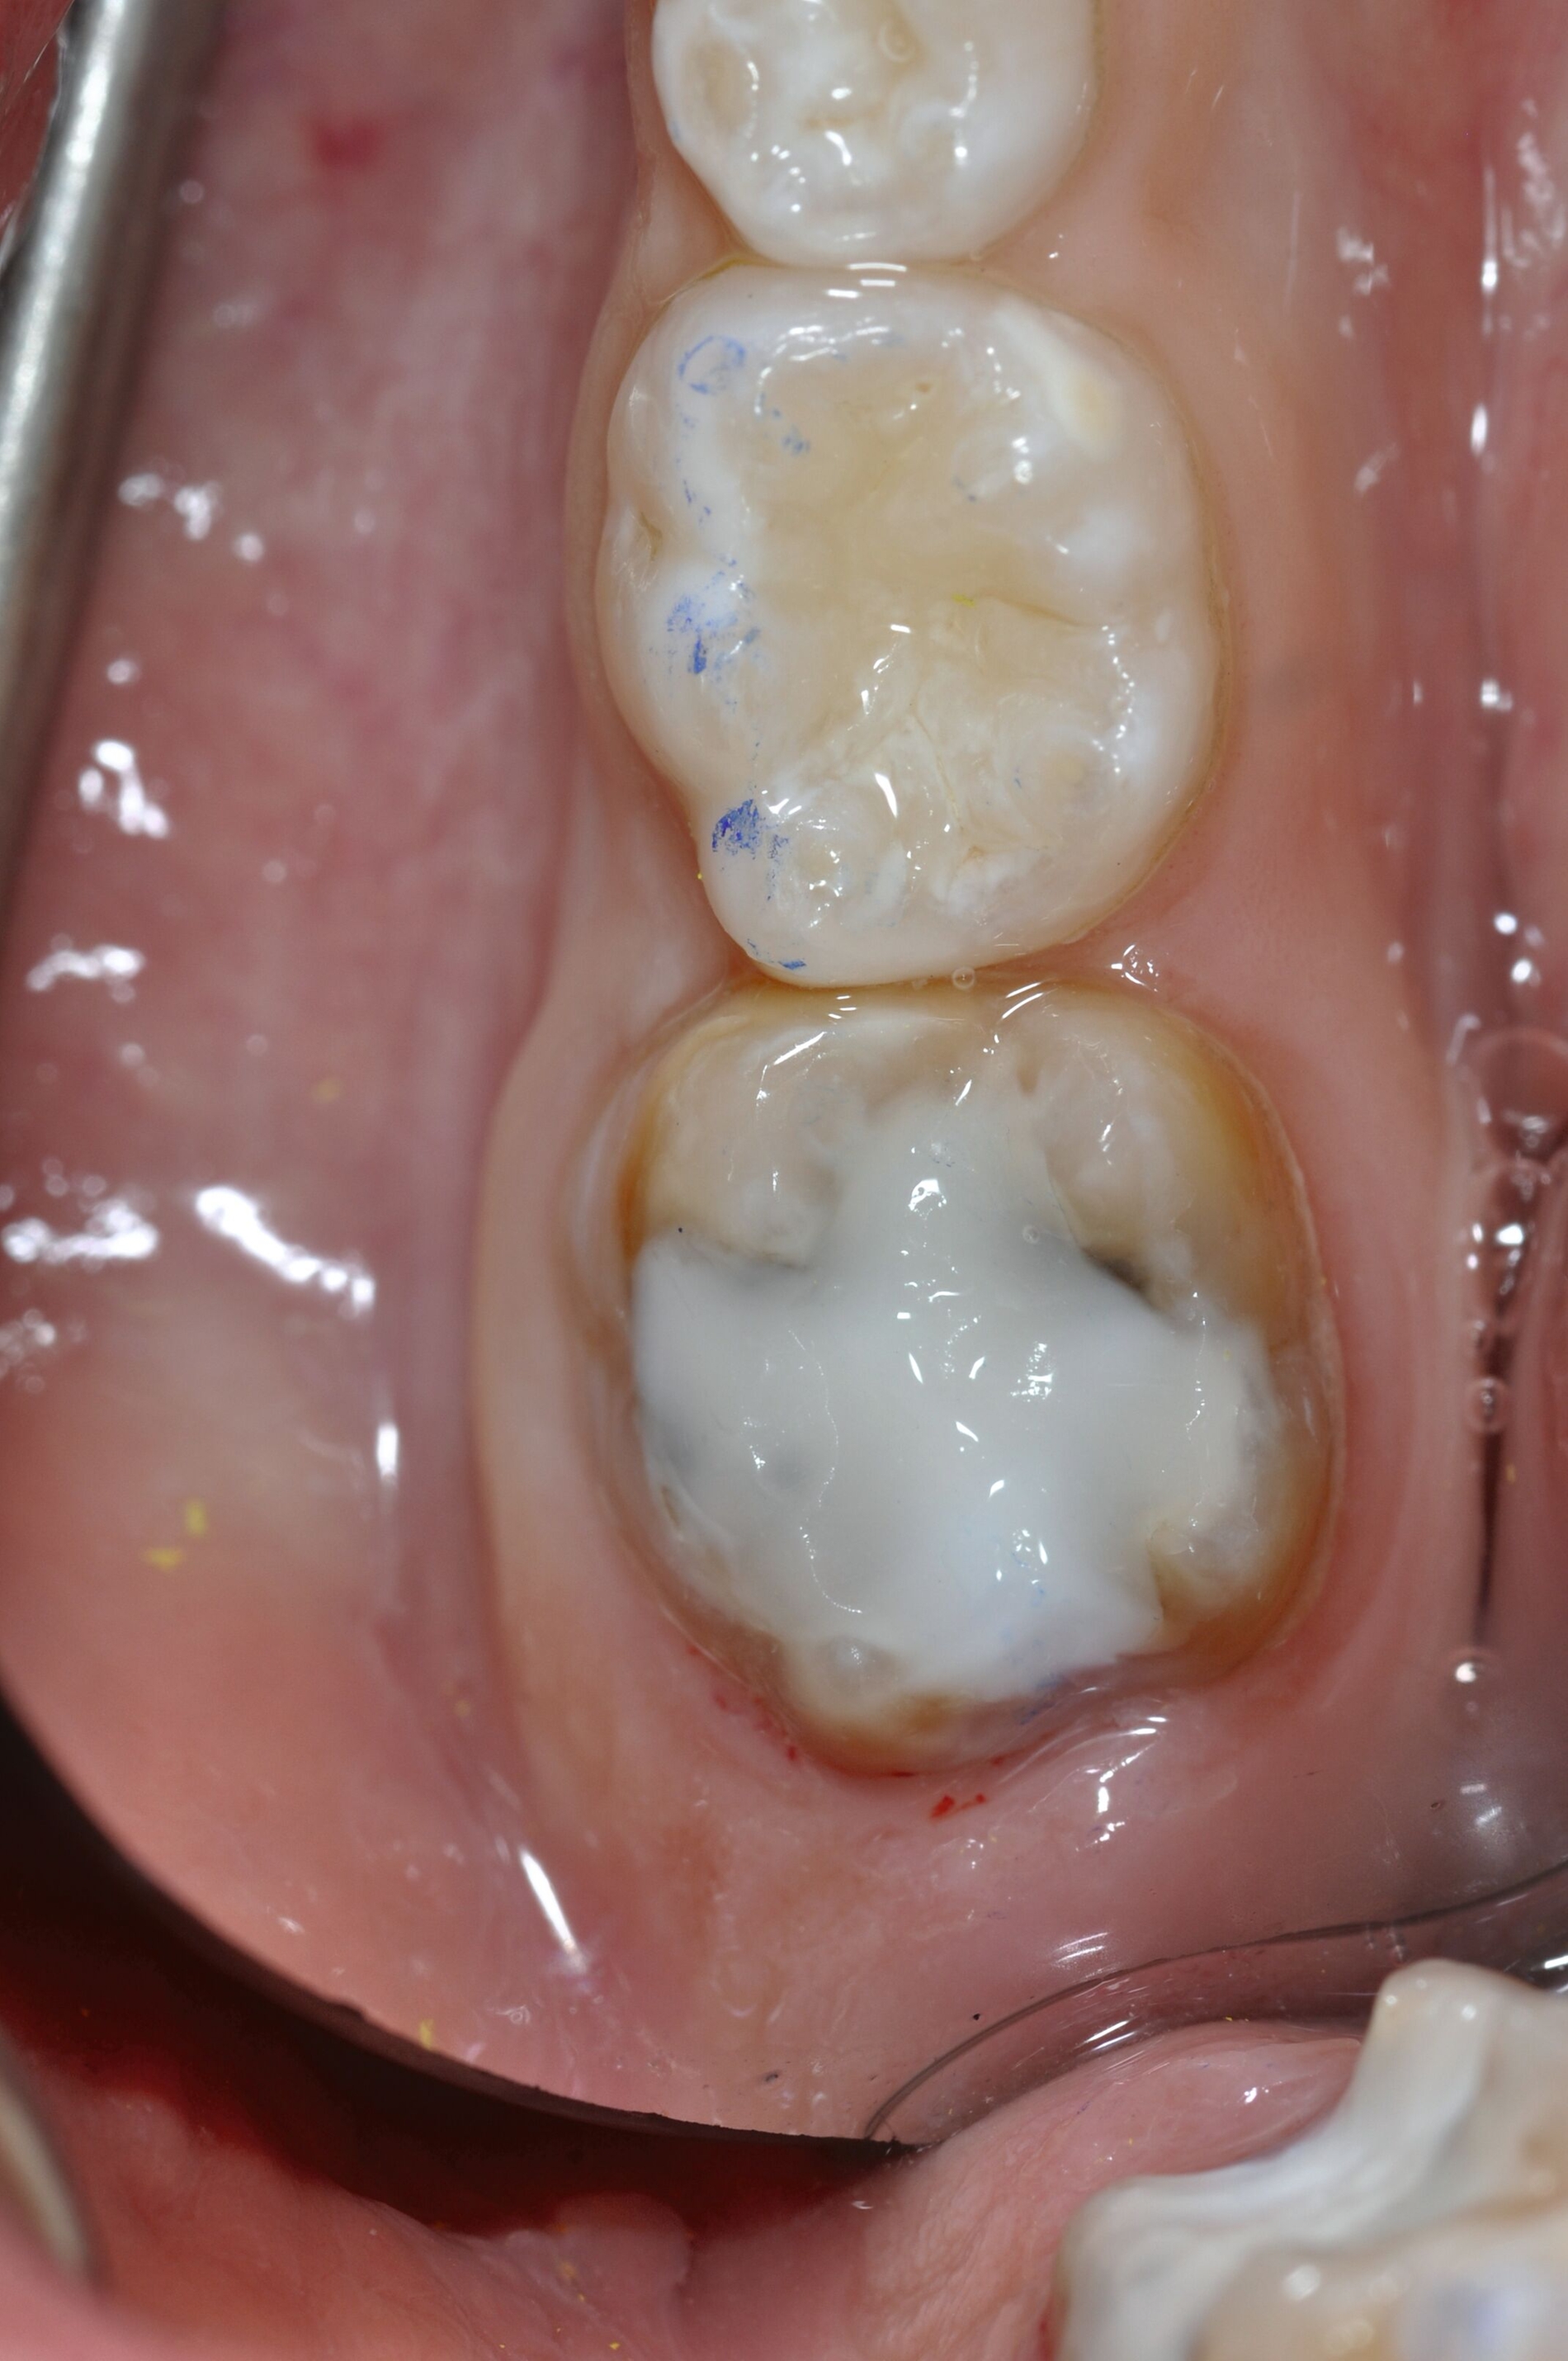

Die direkte Versorgung mit Komposit hat den Vorteil, dass durch die Verwendung von Dentinadhäsiven das Dentin dicht versiegelt werden kann. Hypersensitivitäten werden dadurch deutlich reduziert. Zudem kann der Zahn bei der direkten Versorgung sehr defektorientiert versorgt werden (Abbildung 7).

Während die Dentinhaftung unterhalb des affektierten Schmelzes vergleichbar mit der von gesundem Dentin ist, funktioniert die Haftung an dem strukturell veränderten Schmelz schlechter. Eigene Untersuchungen haben gezeigt, dass die Haftung an dem porösen, proteinreichen Schmelz stark reduziert ist (Abbildung 8) [Krämer et al., 2018]. Sind die Füllungsränder in dem veränderten Bereich lokalisiert, muss mit Randspalten und Abplatzungen gerechnet werden.

Bei größeren Restaurationen muss man im Laufe der Jahre mit Verfärbungen der Füllungen und mit Abrasionen rechnen. Dies spielt insbesondere eine Rolle, wenn im Seitenzahnbereich Höcker ersetzt werden müssen, da Kompositfüllungen mit Höckerersatz an MIH-Molaren eine etwas geringere durchschnittliche Überlebenszeit in der Mundhöhle haben als solche ohne Höckerrekonstruktion [Rolim et al., 2021].